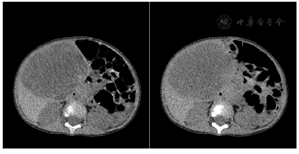

CT图像显示肝右前叶见一巨大囊实性肿物,大小约83mm×63mm×99mm,肿物以囊性成分为主,见粗细不均匀分隔,实性成分呈结节状、斑片状向囊腔内突出,增强后分隔及实性成分见轻度强化,肿物内见纤细血管影,肿块下方部分向腹腔内突出,边界清楚,内壁光滑(图1和图2)。患者随后行"剖腹探查,肝癌切除,胆囊切除,门静脉探查术",冰冻病理示:形态较符合间叶性错构瘤。石蜡切片示肝组织内可见大量疏松水肿的纤维结缔组织明显增生伴粘液样变,其内见萎缩的肝细胞岛,形态符合肝间叶性错构瘤。

DECT采用选择性光子屏蔽(SPS Ⅱ)技术,在70kV和150kV的电压组合下实现能谱的显著分离。使用syngo.CT DE Virtual Unenhanced生成碘图/VNC融合图像,能显著提高血管和肿瘤的观察能力(图1和图2)。虚拟non-contrast(VNC)图像与常规平扫图像一致性匹配(图3),VNC可取代平扫,减少扫描次数做到降低总的剂量,提高合规管理和安全的儿童CT扫描使用。使用syngo.CT DE Monoenergy Plus,在这两个kV设置下获得的衰减值用于显示不同keV水平的图像。与在120kV下采集的常规CT图像相比,低keV的图像对比度显著增强,使得肿瘤侵犯的范围显示更加清晰(图4),低keV图像对比度是非常优异的(图5)。DECT的优势在于搭配西门子CT独有的水冷球管系统,双能力模式中两套球管独立工作,在同一辐射剂量的水平下,在不影响扫描流程和在不增加设备损耗的前提下,实现常规剂量成像,图像质量优异。70/Sn150kV的电压组合是目前用于儿童能量成像的最优参数设置。为了实现儿童低剂量能量检查,其他先进的技术也被使用,如CARE Dose 4D(实时自动曝光控制)和ADMIRE(高级模型迭代重建)。在本病例中,儿童多期CT检查,其中平扫、动脉期和静脉期用双能量技术,延迟期用自由呼吸大螺距技术,多期联扫总的辐射剂量仅为2.85mSv,为传统CT检查的2/5。